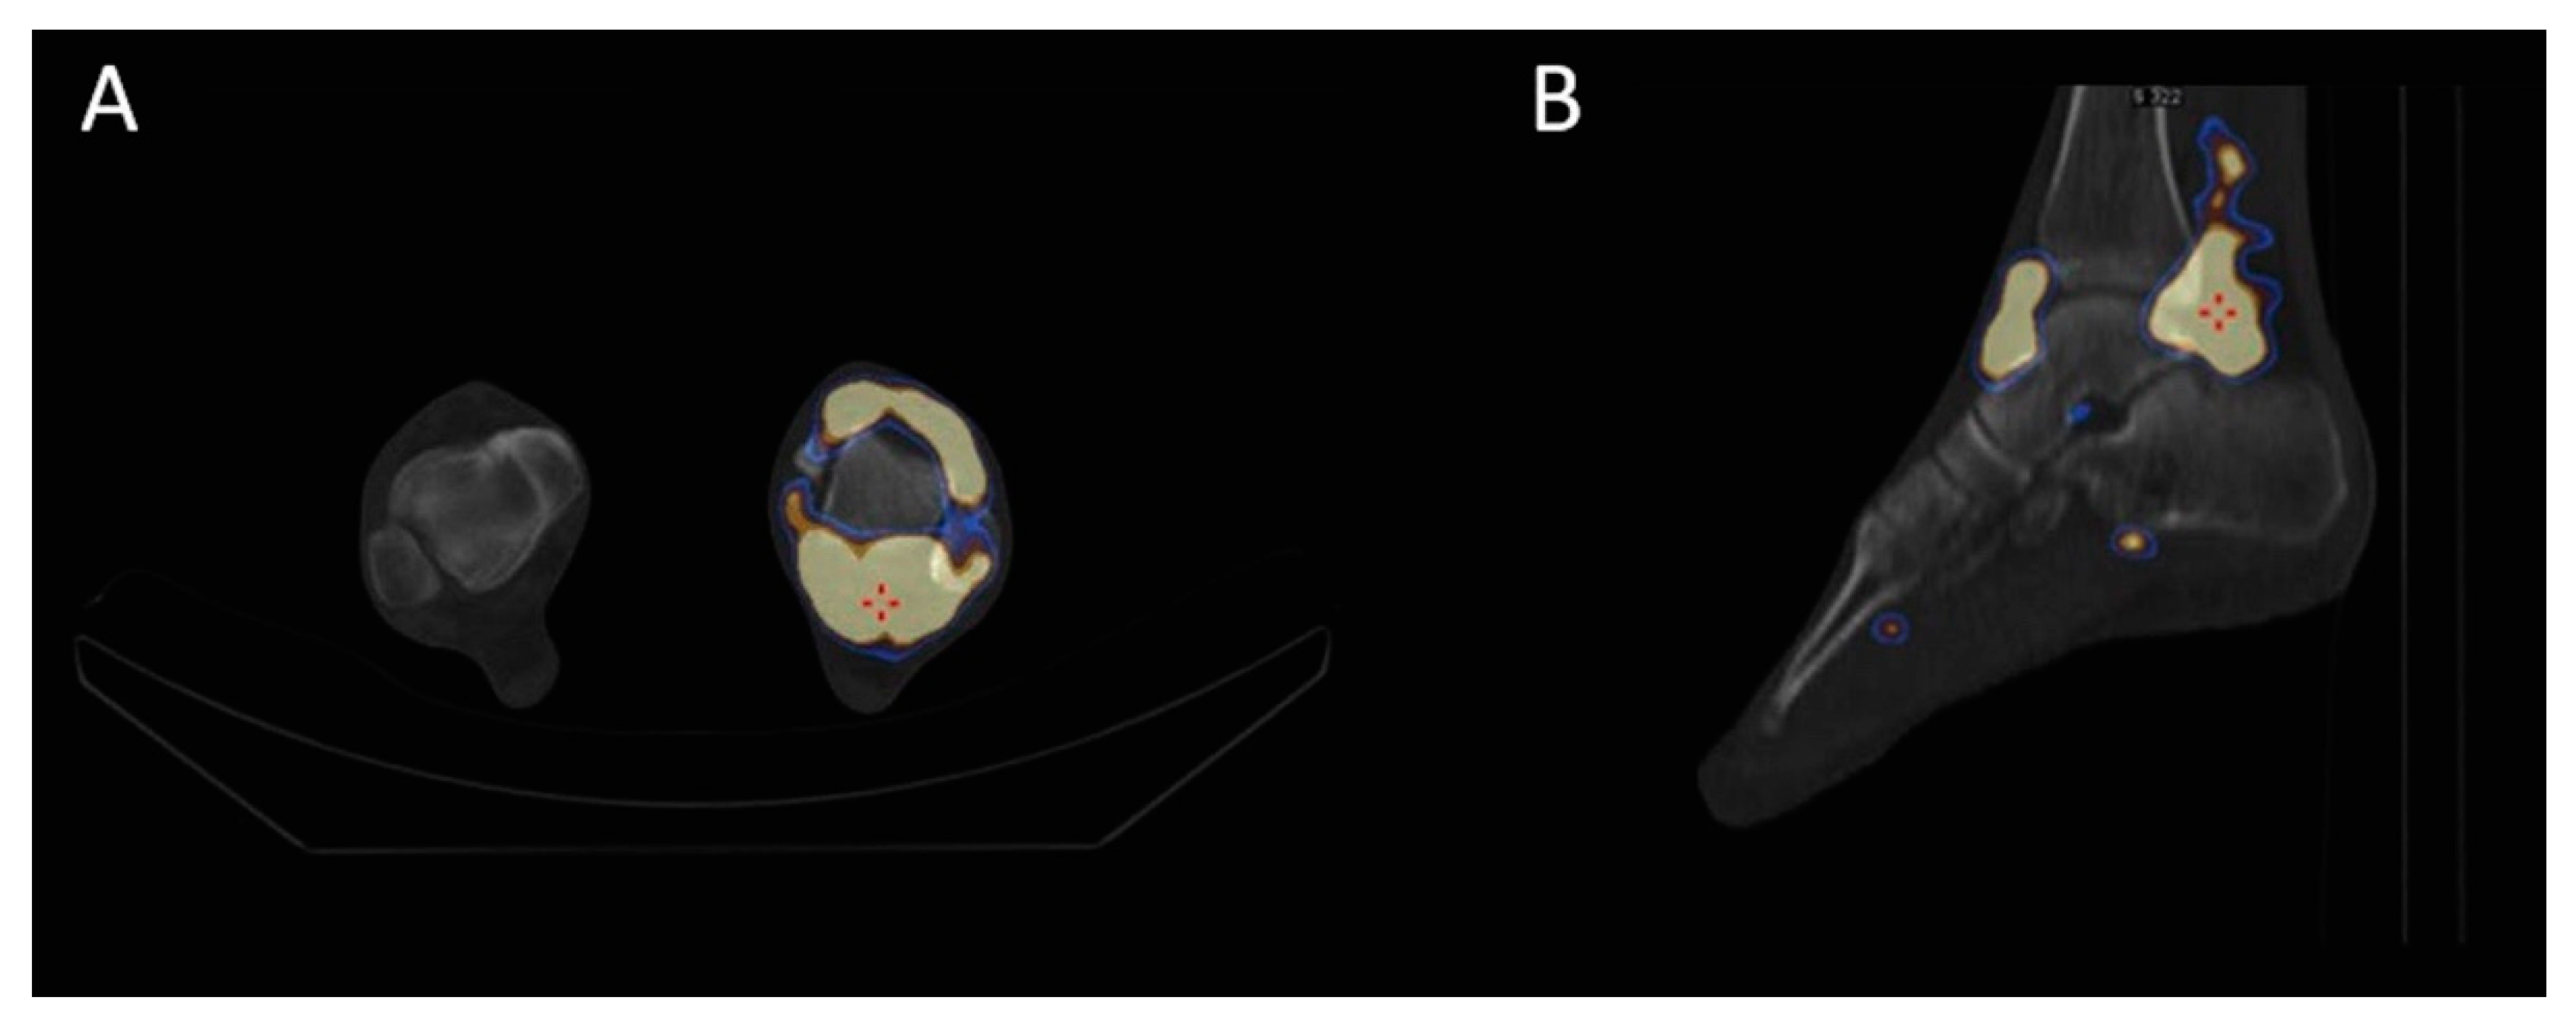

2.3. Radiosynoviorthesis (RSO)